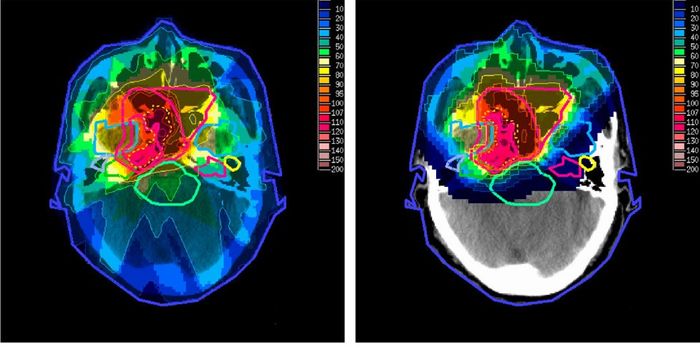

OCT 10, 2016Clinical & Molecular DXA new technique under Phase 1 clinical trial gave surgeons the ability to see a brain tumor glow like they’ve neve ...

SEP 07, 2016CancerFor years, the standard of care for people whose lung cancer has spread to the brain was to administer brain radiotherap ...